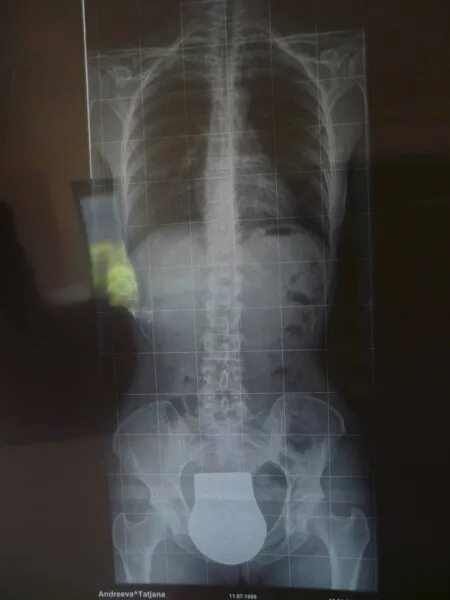

Можно делать рентген при температуре ребенку